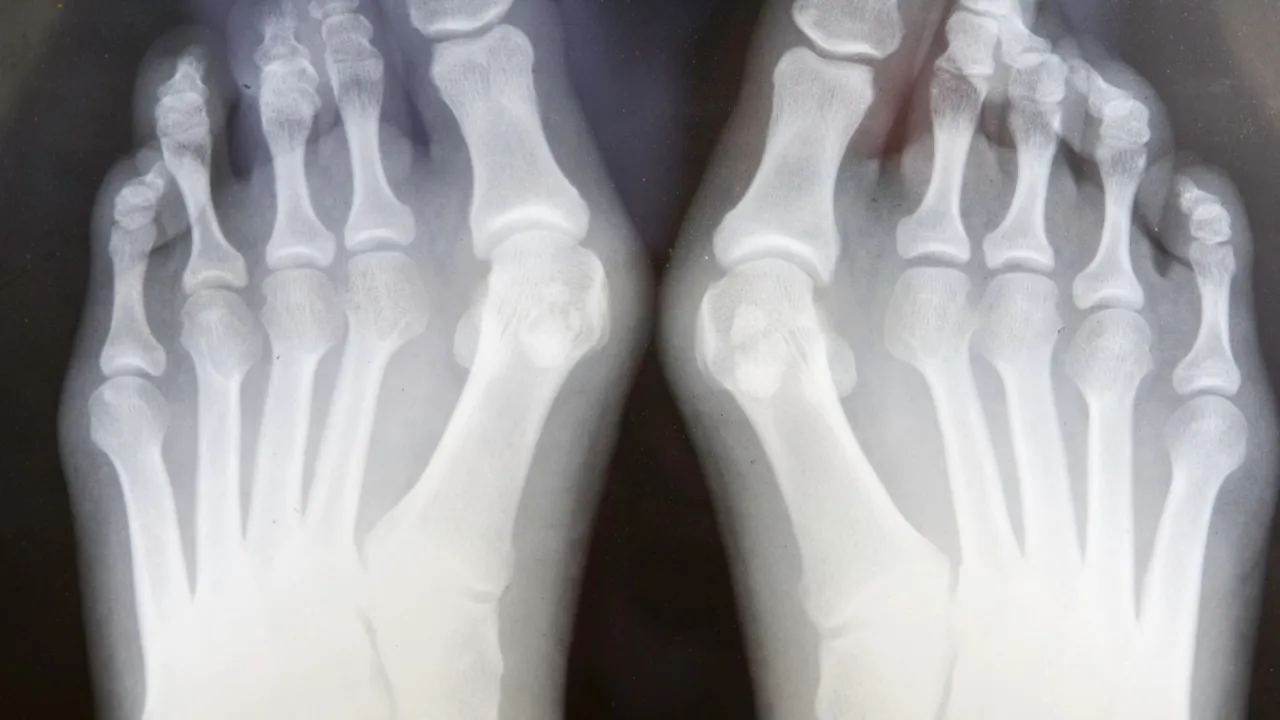

Badanie RTG na stojąco: dlaczego to kluczowy element diagnostyki?

Badanie RTG stóp jest absolutnie niezbędne w diagnostyce haluksów. Co ważne, powinno być wykonane w obciążeniu, czyli na stojąco, w projekcji grzbietowo-podeszwowej i bocznej. Dlaczego? Tylko w takiej pozycji, gdy stopa jest obciążona ciężarem ciała, możemy realnie ocenić stopień deformacji. Zdjęcia wykonane na leżąco mogą nie oddawać pełnego obrazu problemu, ponieważ kości w stopie układają się inaczej pod wpływem nacisku. To badanie dostarcza mi precyzyjnych informacji o strukturze kostnej i pozwala zaplanować optymalną strategię leczenia.

Analiza kątów deformacji: co lekarz widzi na zdjęciu rentgenowskim?

Na zdjęciach rentgenowskich oceniam szereg parametrów, które są kluczowe dla postawienia diagnozy i wyboru metody operacyjnej. Najważniejsze z nich to kąt koślawości palucha (HVA hallux valgus angle) oraz kąt międzypalcowy (IMA intermetatarsal angle). HVA mierzy stopień odchylenia palucha od osi stopy, natomiast IMA wskazuje na rozchylenie pierwszej i drugiej kości śródstopia. Analiza tych kątów, w połączeniu z oceną stanu stawu śródstopno-paliczkowego i ewentualnych zmian zwyrodnieniowych, pozwala mi precyzyjnie dobrać technikę operacyjną, która będzie najbardziej efektywna w Twoim przypadku.